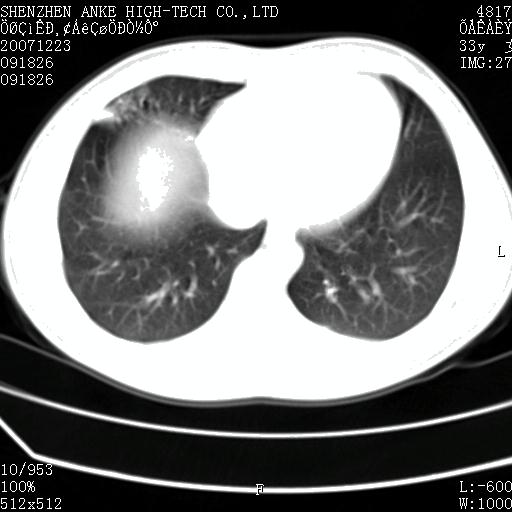

患者:男,19岁,长期咳嗽,咯血3年余,近2月渐渐感觉右侧胸部涨痛不适.2年前胸片见右下肺见片状高密度影,长期抗炎治疗无明显效果.痰菌培养阴性.

右下肺片状实变影,,密度不均,内见含气支气管征及柱状支气管扩张。多考虑:右下肺支气管扩张伴感染!

右肺中叶外侧段大片状高密度影影内可见小圆形透亮影;右肺中叶支扩伴感染。

右肺中叶外侧段大片状不均匀性高密度影影内可见小圆形透亮影;右肺中叶支扩伴感染可能。

右肺中叶支扩伴感染可能大,不除外结核.

建议ppd试验,除外结核,虽不是结核的好发部位,但随着结核的发病率增高,非好发部位结核的发病率也越来越多,且该患者抗炎效果不佳。